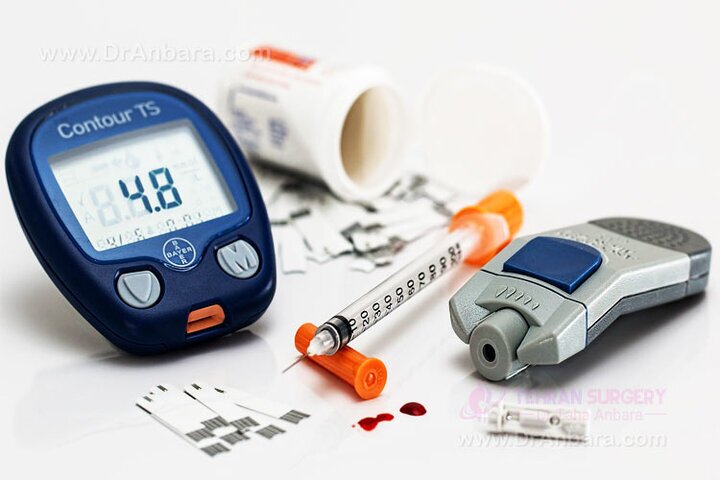

۱۴ درصد جمعیت ایران مبتلا به دیابت هستند

آفتاب نیوز : زهره شرکا عصر جمعه در همایش دیابت و تندرستی که در سالن همایش کتابخانه عمومی قلم برگزار…